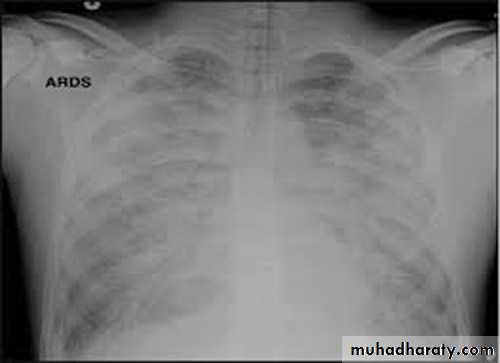

ARDS ( acute respiratory distress syndrome )

The cause is not definite. Hypothesized to be by release of Inflammatory cells and proteinaceous fluid that accumulate in the alveolar spaces leading to a decrease in diffusing capacity and hypoxemia. Usually within the first 24 hours after injury.Clinical features :

-Tachypnea , hypoxia

-X- ray- diffused pulmonary infiltrates

Treatment is by 100% O2 and assisted ventilation

• If not detected early and treated , death may occurs by multiorgan failure or cardiorespiratory failure.